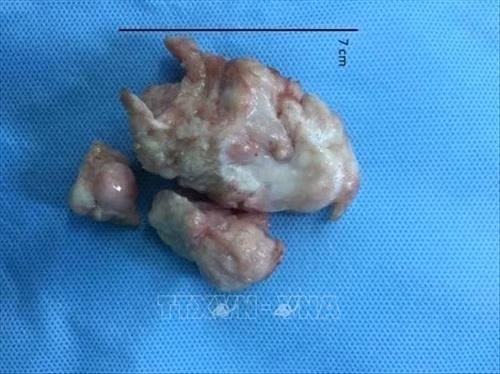

Tiến sỹ, bác sỹ Cao Đằng Khang, Phó trưởng Khoa Phẫu thuật tim mạch – Bệnh viện Đại học Y dược Thành phố Hồ Chí Minh cho biết, bé L.B.P có khối u rất lớn, chiếm gần hết buồng tim thất phải, kích thước 7x4x3,5cm, gây hẹp nặng, cản trở máu lên phổi. Khi máu lên phổi để trao đổi oxy giảm sẽ ảnh hưởng đến sự phát triển thể chất của bé. Ngoài ra, bé có thể bị loạn nhịp tim, gây tử vong đột ngột. Do đó, để tránh các trường hợp nguy hiểm xảy ra cho bé thì hướng điều trị là phải phẫu thuật để cắt bỏ khối u trong tim.

Sau hơn 4 giờ phẫu thuật, toàn bộ khối u có kích thước 7x4x3,5cm đã được lấy ra khỏi tim, phần buồng tim còn lại đã được sửa chữa để đảm bảo chức năng tim được bình thường. “Rất may mắn, kết quả xét nghiệm mô học cho thấy đây là u sợi lành tính, như vậy bệnh nhi sẽ hoàn toàn bình phục với trái tim khỏe mạnh”, bác sỹ Cao Đằng Khang chia sẻ.

Khối u cơ tim lớn có kích thước7x4x3.5cm của bệnh nhi 4 tháng tuổi. Ảnh: TTXVN phát